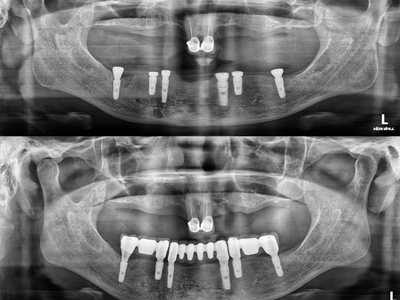

| Áø´Ü | CT¸¦ ÀÌ¿ëÇÏ¿© 3Â÷¿ø Áø´ÜÇÕ´Ï´Ù.

CT ÃÔ¿µÇÑ 3Â÷¿ø µ¥ÀÌÅ͸¦ ÅëÇØ »À, ÀÕ¸ö, ½Å°æÀ» ÅëÇÕÀûÀ¸·Î °í·ÁÇÏ¿© Á¤¹Ð Áø´Ü ÇÕ´Ï´Ù. |

| °èȹ | ÄÄÇ»ÅÍ·Î ¼ö¼ú°èȹÀ» ¼ö¸³ÇÕ´Ï´Ù.

ÄÄÇ»ÅÍ·Î ¸ðÀÇ ¼ö¼úÀ» ÅëÇØ ÃÖÀûÀÇ ÀÓÇöõÆ® ½Ä¸³ À§Ä¡¸¦ ¼³Á¤Çϰí, ±×´ë·Î ¼ö¼úµÉ ¼ö ÀÖµµ·Ï ȯÀÚ ¸ÂÃãÇü °¡À̵带 Á¦ÀÛÇÕ´Ï´Ù. |

| ¼ö¼ú | °¡À̵å ÀåÂø ÈÄ ¼ö¼úÇÕ´Ï´Ù.

Á¦ÀÛÇÑ ³×ºñ°ÔÀÌ¼Ç °¡À̵带 ¼ö¼ú Àü ±¸°¿¡ ÀåÂøÇÑ µÚ °èȹÇÑ À§Ä¡¿¡ Á¤È®ÇÏ°Ô ¼ö¼úÇÕ´Ï´Ù. |

| ½Ä¸³ | °èȹÇÑ À§Ä¡¿¡ ½Ä¸³ÇÕ´Ï´Ù.

¸ðÀǼö¼ú·Î °èȹÇÑ À§Ä¡¿¡ Á¤È®ÇÏ°Ô ÀÓÇöõÆ®°¡ ½Ä¸³µË´Ï´Ù. ³» Ä¡¾Æ°°Àº º¸Ã¶¹°·Î ÀÚ¿¬½º·´°Ô Á¦À۵˴ϴÙ. |